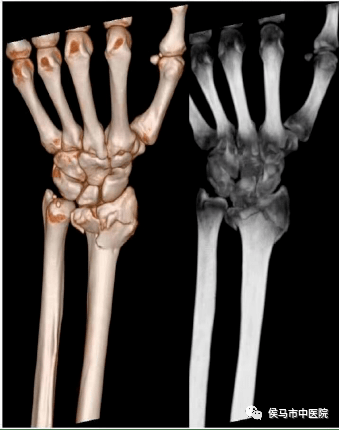

7、全身各部位骨三维重建

该设备强大的后处理软件,能对全身各部位骨三维立体快速成像,清晰显示骨结构的细微结构,对骨折及内固定显示清晰、直观,能更好地为临床服务。